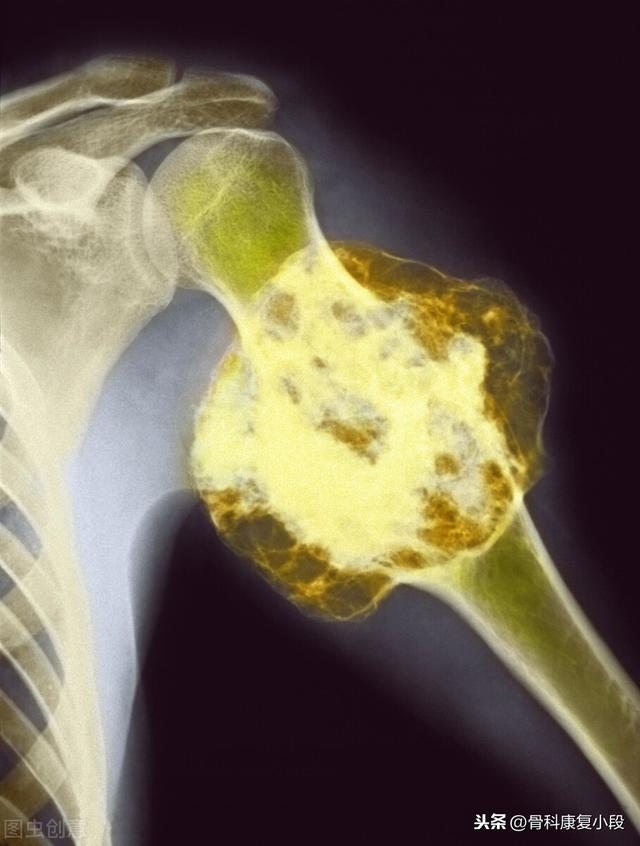

5年間生存している低分化癌の鎖骨転移

この症例は58歳のゲイ男性で、肩を軽く伸ばしただけで痛みが続くようになり、X線検査で低密度病巣が見つかった:

これは骨転移に基づく軽微な外力による病的骨折であった。穿刺が行われ、病理結果は低分化肺腺癌の骨転移であった。

骨転移で起こる症状にはどのようなものがありますか?最初の症状は痛みです。骨転移を起こした部位は骨が破壊されるために痛みを感じますが、最初ははっきりした症状がなかったり、断続的な痛みだったりしますが、腫瘍が正常な骨をどんどん破壊して徐々に悪くなっていくため、転移部位の痛みも徐々に悪くなっていきます。臨床的には、体のある部分の骨の痛みで、悪性腫瘍の骨転移という症例に出くわすことがあります。以前、ある症例に出会ったのですが、40歳で、肩が痛く、五十肩かと思い、薬用オイルを数日揉んでも改善が見られず、ますます痛みが強くなったので、病院で検査をしたところ、MRIを撮ったところ、肩甲骨が(腫瘍の)かけらに食べられており、骨転移を考え、胸部CTを撮ったところ、右肺に結節があり、生検をして病理検査をしたところ、肺がんの骨転移でした。その内容は以下の通りである。

骨転移部位では、正常な骨組織が破壊され腫瘍組織に置き換わり、腫瘍細胞は常に増殖しているため、多くの骨転移部位で軟部組織の腫瘤影が見られ、腫瘤が表在する部位であれば触知することができる。また、腫瘍組織による正常な骨組織の侵食は、正常な骨構造の破壊と脆弱化につながるため、正常な外力下でも骨折が生じることがあり、病的骨折と呼ばれます(下図)。脊椎への転移は、疼痛や病的骨折に加えて、脊髄神経根の圧迫を伴い、感覚障害、筋力低下、場合によっては高カルシウム血症などの症状を呈することもあります。